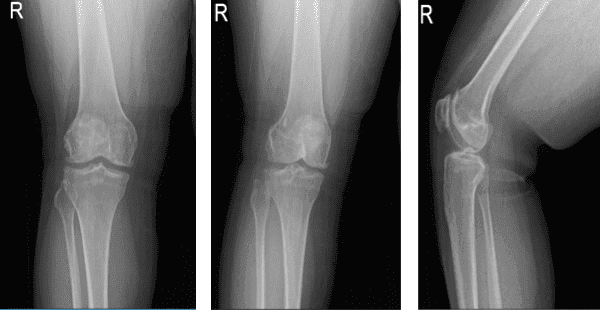

Se realizaron radiografías, el fémur distal, la rótula, la tibia proximal y el peroné proximal demuestran márgenes corticales intactos sin fractura aguda. Los espacios de la articulación medial, lateral y patelofemoral están bien mantenidos. Hay una formación leve de osteófitos mediales. Hay una formación leve de osteófitos patelofemorales.

No hay evidencia radiográfica de derrame articular. No hay evidencia radiográfica de hinchazón de tejidos blandos. La impresión es que hay cambios degenerativos osteoartríticos leves. No hay fracturas agudas.

Que mostró una inclinación lateral de la rótula hacia la troclea junto con artritis patelofemoral avanzada con artritis compartimental medial leve. Además, se realizó la resonancia magnética para confirmar los hallazgos.

Rayos X de rodilla derecha AP Vistas laterales y oblicuas 3